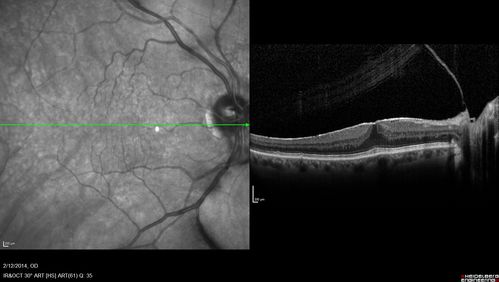

Macular Hole Left Eye - progression from VMT - Stage II macular hole - Spontaneously Closed Macular Hole

Macular Hole from Vitreomacular traction to Stage II hole to Spontaneously Closed Hole